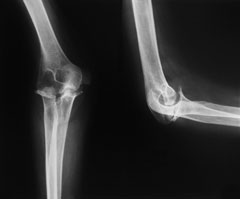

Ostéoporose

Le magazine fait le point sur les bienfaits et méfaits du soleil. Parmi les points positifs, il note que le soleil « est bon pour le moral », «bon pour la peau », et que grâce à lui, « on dort mieux ». Il souligne aussi qu’il permet de synthétiser la vitamine D : « c'est le soleil (et plus spécifiquement les UVB) qui permet ce processus particulièrement important chez les personnes plus âgées et les enfants. Le calcium peut ainsi aider nos os à lutter contre les dangers de l'ostéoporose, mais aussi contribuer à l'élimination du rachitisme chez les plus jeunes », explique-t-il. « Une bonne croissance et résistance du squelette sont donc les deux aspects de cette vitamine D », résume-t-il.

« Fracture du col du fémur : opérer le plus vite possible »

« Le plus important, face à une fracture du col du fémur, c'est d'opérer les patients le plus rapidement possible, dans les 48 heures au plus. C'est un traumatisme qui se produit surtout après 75 ans et la position couchée, à cet âge, peut provoquer de nombreuses complications », rappelle, dans le Figaro, le Pr Sébastien Lustig, chirurgien orthopédiste à l'hôpital de la Croix-Rousse, à Lyon.